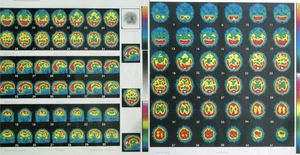

We asked for a magnetic resonance (MR) and a SPECT as complementary tests to see if there were anatomical brain findings of Crow's Type II schizophrenia.15 The patient had already had a brain MR in 2005, without finding any significant alterations. The 2010 MR revealed the presence of slight, predominantly frontal cerebral atrophy (Fig. 3), while a bilateral temporal hypoperfusion was observed in the SPECT (Fig. 4).

It was only after many years of illness, as a conclusion to the patient's evolution, the results from the psychometric tests described above and the findings from the 2 neuroimaging tests helped us to reach the conviction that everything supported the diagnosis of simple schizophrenia.17

Although not always, in various studies on neuromorphological anomalies of patients diagnosed with simple schizophrenia, there are anomalies typical of other schizophrenia subtypes, such as greater ventricular and subarachnoid space volumes, as well as further alterations in brain development.23–25 Studies on visual evoked potentials show alterations in various subtypes of patients with schizophrenia, including those who received the diagnosis of simple schizophrenia.26 Functional neuroimaging tests like the SPECT can demonstrate a deficit of perfusion in the frontal regions, associated with aspects of schizophrenia such as chronicity, presence of a negative clinical syndrome and cognitive deterioration17. This hypoperfusion of the prefrontal grey matter has also been found in more recent studies, such as Suzuki's.27

This is a disorder that, psychopathologically speaking, can present with a low symptom profile (in the case we describe, the personality test results oscillated from very pathological, in 2005, and normal, in 2010). Consequently, using tests for functional and neuropsychological deterioration, as well as functional neuroimaging tests, can be very useful for diagnosing it.18